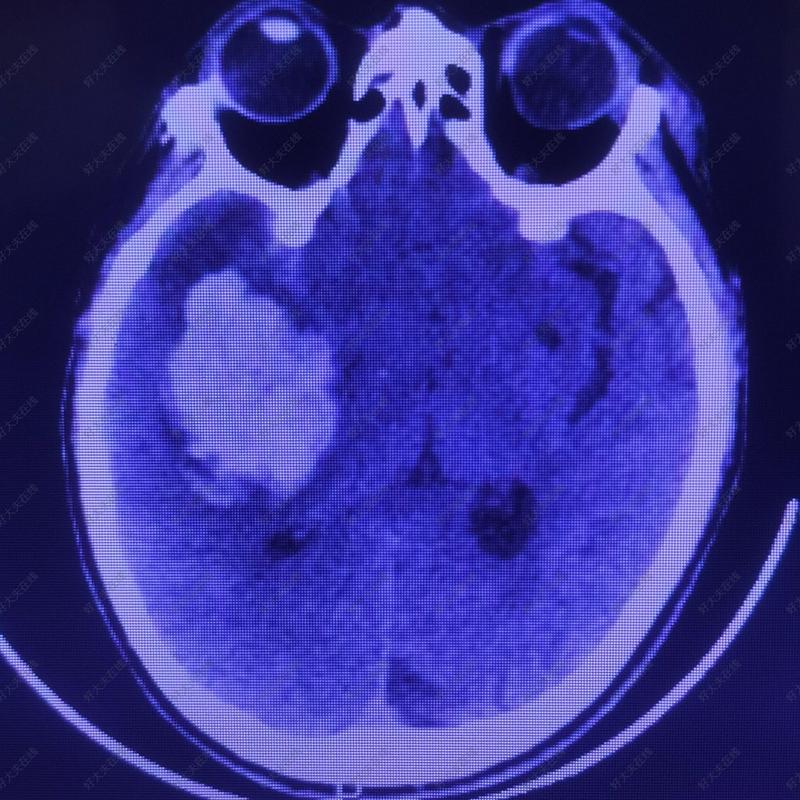

治療前突發(fā)意識障礙并肢體偏癱,急診CT示右側(cè)基底節(jié)出血,出血量約60ml。急診開顱手術(shù)治療。治療中小切口,小骨瓣開顱,經(jīng)外側(cè)裂將血腫清除,骨瓣復(fù)位。手術(shù)創(chuàng)傷小,血腫清除及時(shí)徹底,患者術(shù)后恢復(fù)快,不用去骨瓣二次手術(shù)顱骨修補(bǔ)。治療后治療后30天傷口愈合良好,神志清醒,遺留左側(cè)一會不全癱瘓康復(fù)治療后好轉(zhuǎn)。治療后0天復(fù)查CT顯示血腫徹底清除,患者意識較術(shù)前明顯好轉(zhuǎn)。

一、醫(yī)生查體: 患者由120送入醫(yī)院后,醫(yī)生首先確定患者生命體征是否平穩(wěn)?判斷患者意識狀態(tài)、瞳孔變化、肢體肌力肌張力、感覺變化、病理征等。 二、常規(guī)檢查及化驗(yàn)(抽血化驗(yàn)): 進(jìn)行常規(guī)的檢查及化驗(yàn)(抽血化驗(yàn)),包括:常規(guī)心電圖、血常規(guī)、血生化、凝血功能、血糖、血脂、肝功能、腎功能及電解質(zhì)、感染四項(xiàng)等,如需開顱手術(shù),還需化驗(yàn)血型并備血。 三、頭顱CT(CT平掃、CTA、CTP等): 患者行頭顱CT檢查時(shí),不要佩戴金屬耳環(huán)、耳釘、項(xiàng)鏈等飾品。頭顱CT平掃為腦出血的首選影像學(xué)檢查方法,CT平掃可快速準(zhǔn)確的顯示出血的部位、出血量、占位效應(yīng)、對周圍腦組織的損傷以及是否破入腦室或蛛網(wǎng)膜下腔、腦水腫程度等,有利于早期與腦梗塞/腦梗死相鑒別。增強(qiáng)CT發(fā)現(xiàn)的造影劑外溢到血腫內(nèi)是提示患者血腫擴(kuò)大高風(fēng)險(xiǎn)的重要證據(jù)。灌注CT(CTP)能夠反映腦出血后腦組織的血流動力學(xué)變化,可了解血腫周邊血流灌注情況。懷疑腦出血非高血壓性腦出血的造成,需行CT血管成像(CTA)進(jìn)一步檢查。 四、頭顱磁共振掃描(MRI): 頭顱MRI檢查有助于提供腦出血更多的信息,但一般不作為急診檢查手段。當(dāng)患者有幽閉恐懼癥或體內(nèi)有金屬植入物(如假牙、心臟支架等),則不行頭顱MRI檢查。 五、腦血管造影檢查: 對于非典型病史或CT表現(xiàn)的患者,行腦血管造影檢查有助于明確腦出血的病因,以排除非高血壓性腦出血的可能(腦動靜脈畸形、腦動脈瘤、煙霧病等)。常用檢查包括數(shù)字減影血管造影(DSA)、CT血管成像(CTA)、磁共振血管成像(MRA)、CT靜脈成像(CTV)、磁共振靜脈成像(MRV)等。 保定市第一中心醫(yī)院是國家衛(wèi)健委高級卒中中心, 保定市第一中心醫(yī)院神經(jīng)外科是保定市醫(yī)學(xué)重點(diǎn)??疲?保定市第一中心醫(yī)院的醫(yī)療設(shè)備(CT/MRI/DSA)等硬件條件具有區(qū)域領(lǐng)先優(yōu)勢, 保定市第一中心醫(yī)院神經(jīng)外一科腦卒中團(tuán)隊(duì)由神經(jīng)外科博士、碩士、主任醫(yī)師等參與構(gòu)建,專業(yè)治療高血壓腦出血等疾病, 我們愿意為您的健康保駕護(hù)航!